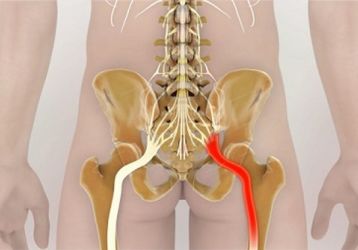

Защемление нерва в тазобедренном суставе: причины, симптомы и лечение ущемления

Каковы причины и симптомы защемления нерва в тазобедренном суставе. Лечение ущемления нерва в ТБС консервативным и хирургическим путем.